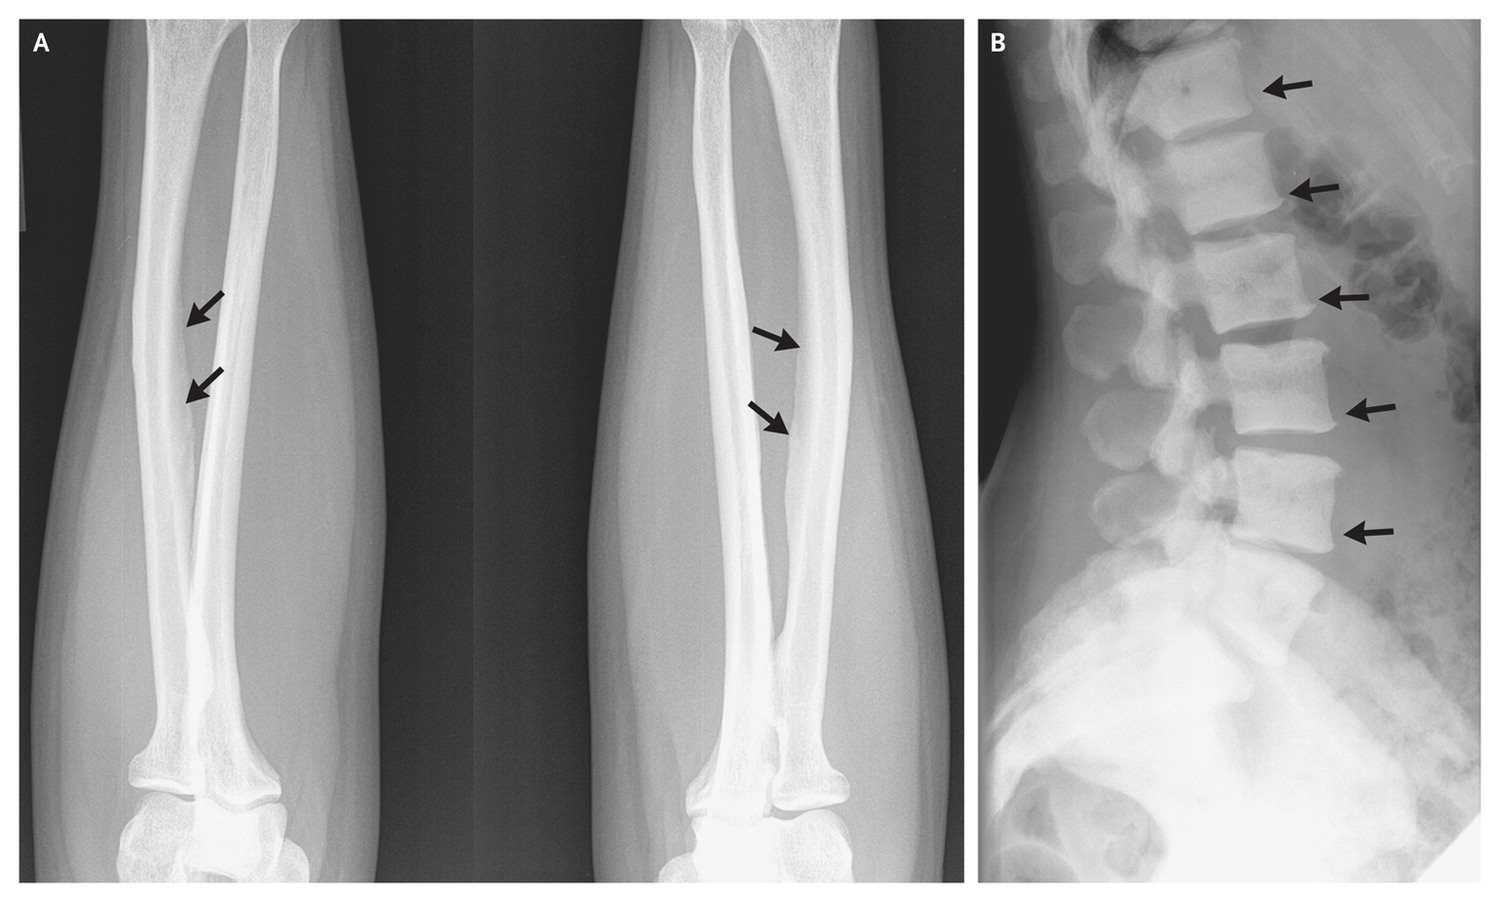

先讲最近新英格兰医学杂志报导的一个病例。患者女性,47岁,嗜茶十七年。近五年来发现腿,手臂,下腰和髋关节严重疼痛。就诊时,牙齿由于太脆,都已断裂而拔光了。X光检查发现她骨膜钙化,骨表面有厚厚的沉淀 (图1)。血液检查发现氟浓度高出正常人四倍多。她患的是骨和牙齿的氟化病。医生根据她的饮茶习惯,估计她每天氟的摄于量大约在20毫克以上。医生嘱她停止喝茶后,症状渐有好转。但完全靠病人自然地清除骨骼里多余的氟,需要几年的时间。医生正考虑进行药物治疗,来加快这一过程。

但我们必须知道,氟是一把双刃剑。过多的氟化钙可使骨骼硬而脆,容易骨折;使关节软骨和韧带硬化,导致畸形,如踝膝内翻,下肢交剪,弓背等等(图2和3)。当氟化钙过多时,机体会清除氟化钙,从而又会使骨骼失去钙,导致骨骼疏松。过多的氟沉积在牙齿表面,可使牙齿呈现白斑,或变成褐色,且脆而易断(图4和5)。

(图1来自New England Journal of Medicine, 其余来自网络)(96)

Fig。 1.